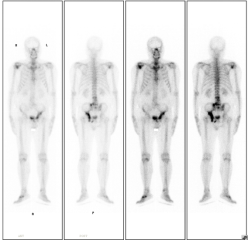

患者老年男性,因前列腺癌骨转移伴明显疼痛,于2022年8月行全身骨显像,后给予锶89及唑来膦酸等联合治疗,疼痛明显缓解,于2023年5月行全身骨显像复查,病灶明显减少、范围缩小、病灶活跃程度减低。